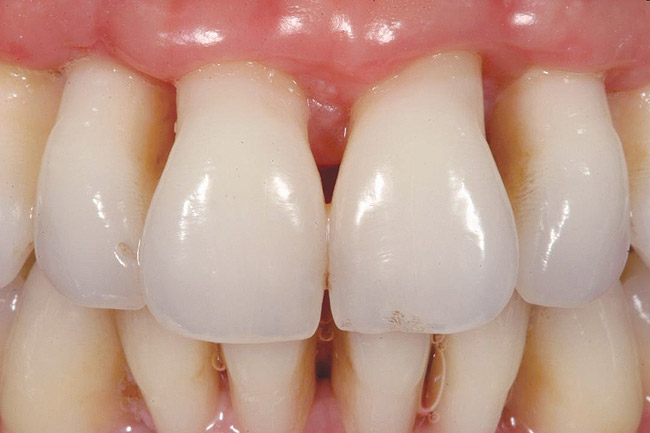

To achieve an esthetic result, it is advantageous to have papillary symmetry between contralateral sides of the dentition and avoidance of short papillae between implants. Tarnow et al67 demonstrated that implants should be placed at least 3 mm apart to avoid bone loss, which can result in recession of papillae. In a later study, Tarnow and colleagues68 noted that the average height of a papilla between two implants was 3.4 mm and that > 50% of the papillae between implants were ≤ 3 mm in height (Figure 4).68 Therefore, to attain the best esthetics, if two adjacent implants are to be placed, modification of the treatment plan may be necessary. If possible, consideration should be given to saving one tooth to avoid short papillae.

Figure 4  The average height of a papilla between 2 implants is 3.4 mm. Note the short papilla between implant-supported crowns on teeth Nos. 9 and 10.

Figure 4